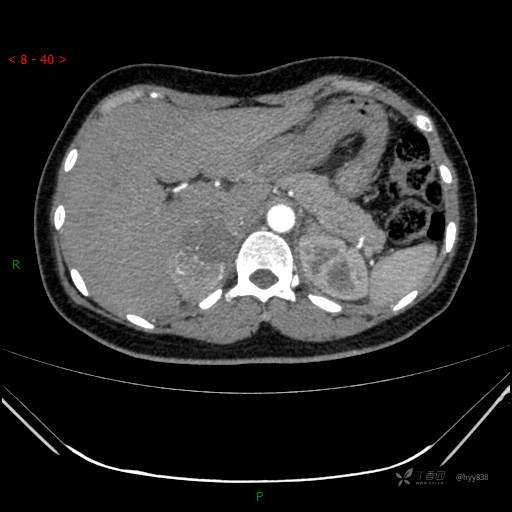

静脉期